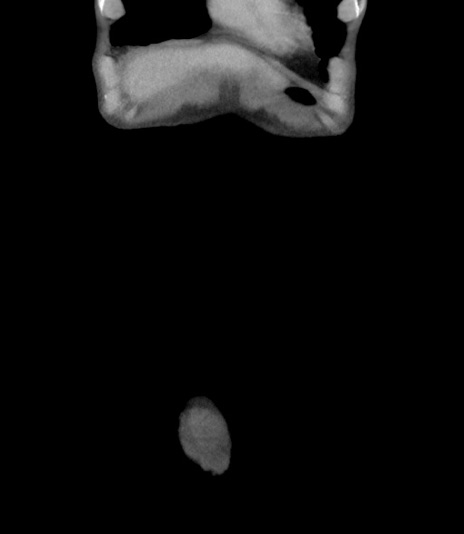

矢状断像

【症例】 70歳代男性

【主訴】右鼠径部腫瘤、疼痛

【既往歴】膀胱癌にて膀胱全摘、両側尿管皮膚瘻